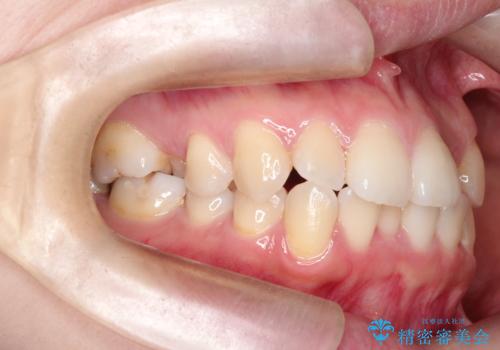

- 主訴:口元を下げて前突感を無くしたい、下の歯の凹凸も無くしたい

右側第二小臼歯、左側第一小臼歯、下顎両側第一小臼歯を抜歯しワイヤ-矯正を行いました。

骨格的顎の変位を認めたため、顔貌に対しピッタリ上下の歯の正中を合わせることは難しいと説明し、上下左右計4本小臼歯を抜歯しワイヤー矯正治療を行いました。